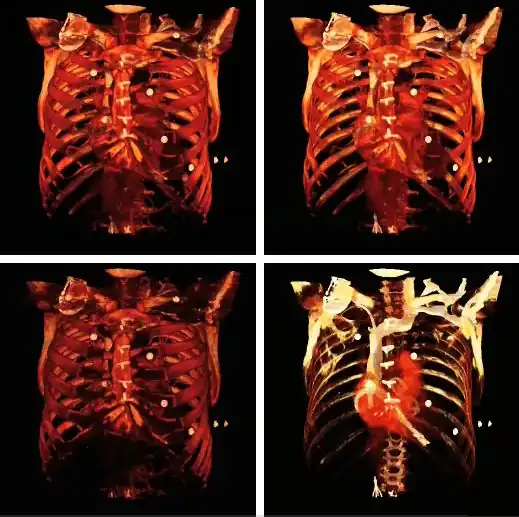

- Volume rendering can be applied to the voxel data in the successive rotation manner described for MIPs above, as illustrated in Figure 5.25. A superior display to that of MIPs is clearly evident.

- Note that the volume rendering can be contrast enhanced so as to threshold, for instance, through the voxel values to eliminate lower attenuation surfaces, as illustrated in Figure 5.26.

- Note also that the colour look-up table (CLUT) can be varied to highlight features of particular interest, as shown in the set of images in Figure 5.27. A vast range of CLUTs is available with the four shown being used here solely for illustrative purposes.

- The influence of the opacity table is illustrated in Figure 5.28, which shows (from top left to bottom right) the effect of linear, exponential, logarithmic and non-linear functions.

- A final feature to note about volume rendering is that 3D editing techniques can be applied so as to exclude unwanted features from the computations and to expose internal structure. This is illustrated in Figure 5.29, where planes of an orthogonal frame can be moved to crop voxel data in just one direction to reveal the aorta (top right), for example, or in multiple directions to inspect the transplanted kidney (bottom right), as a second example.